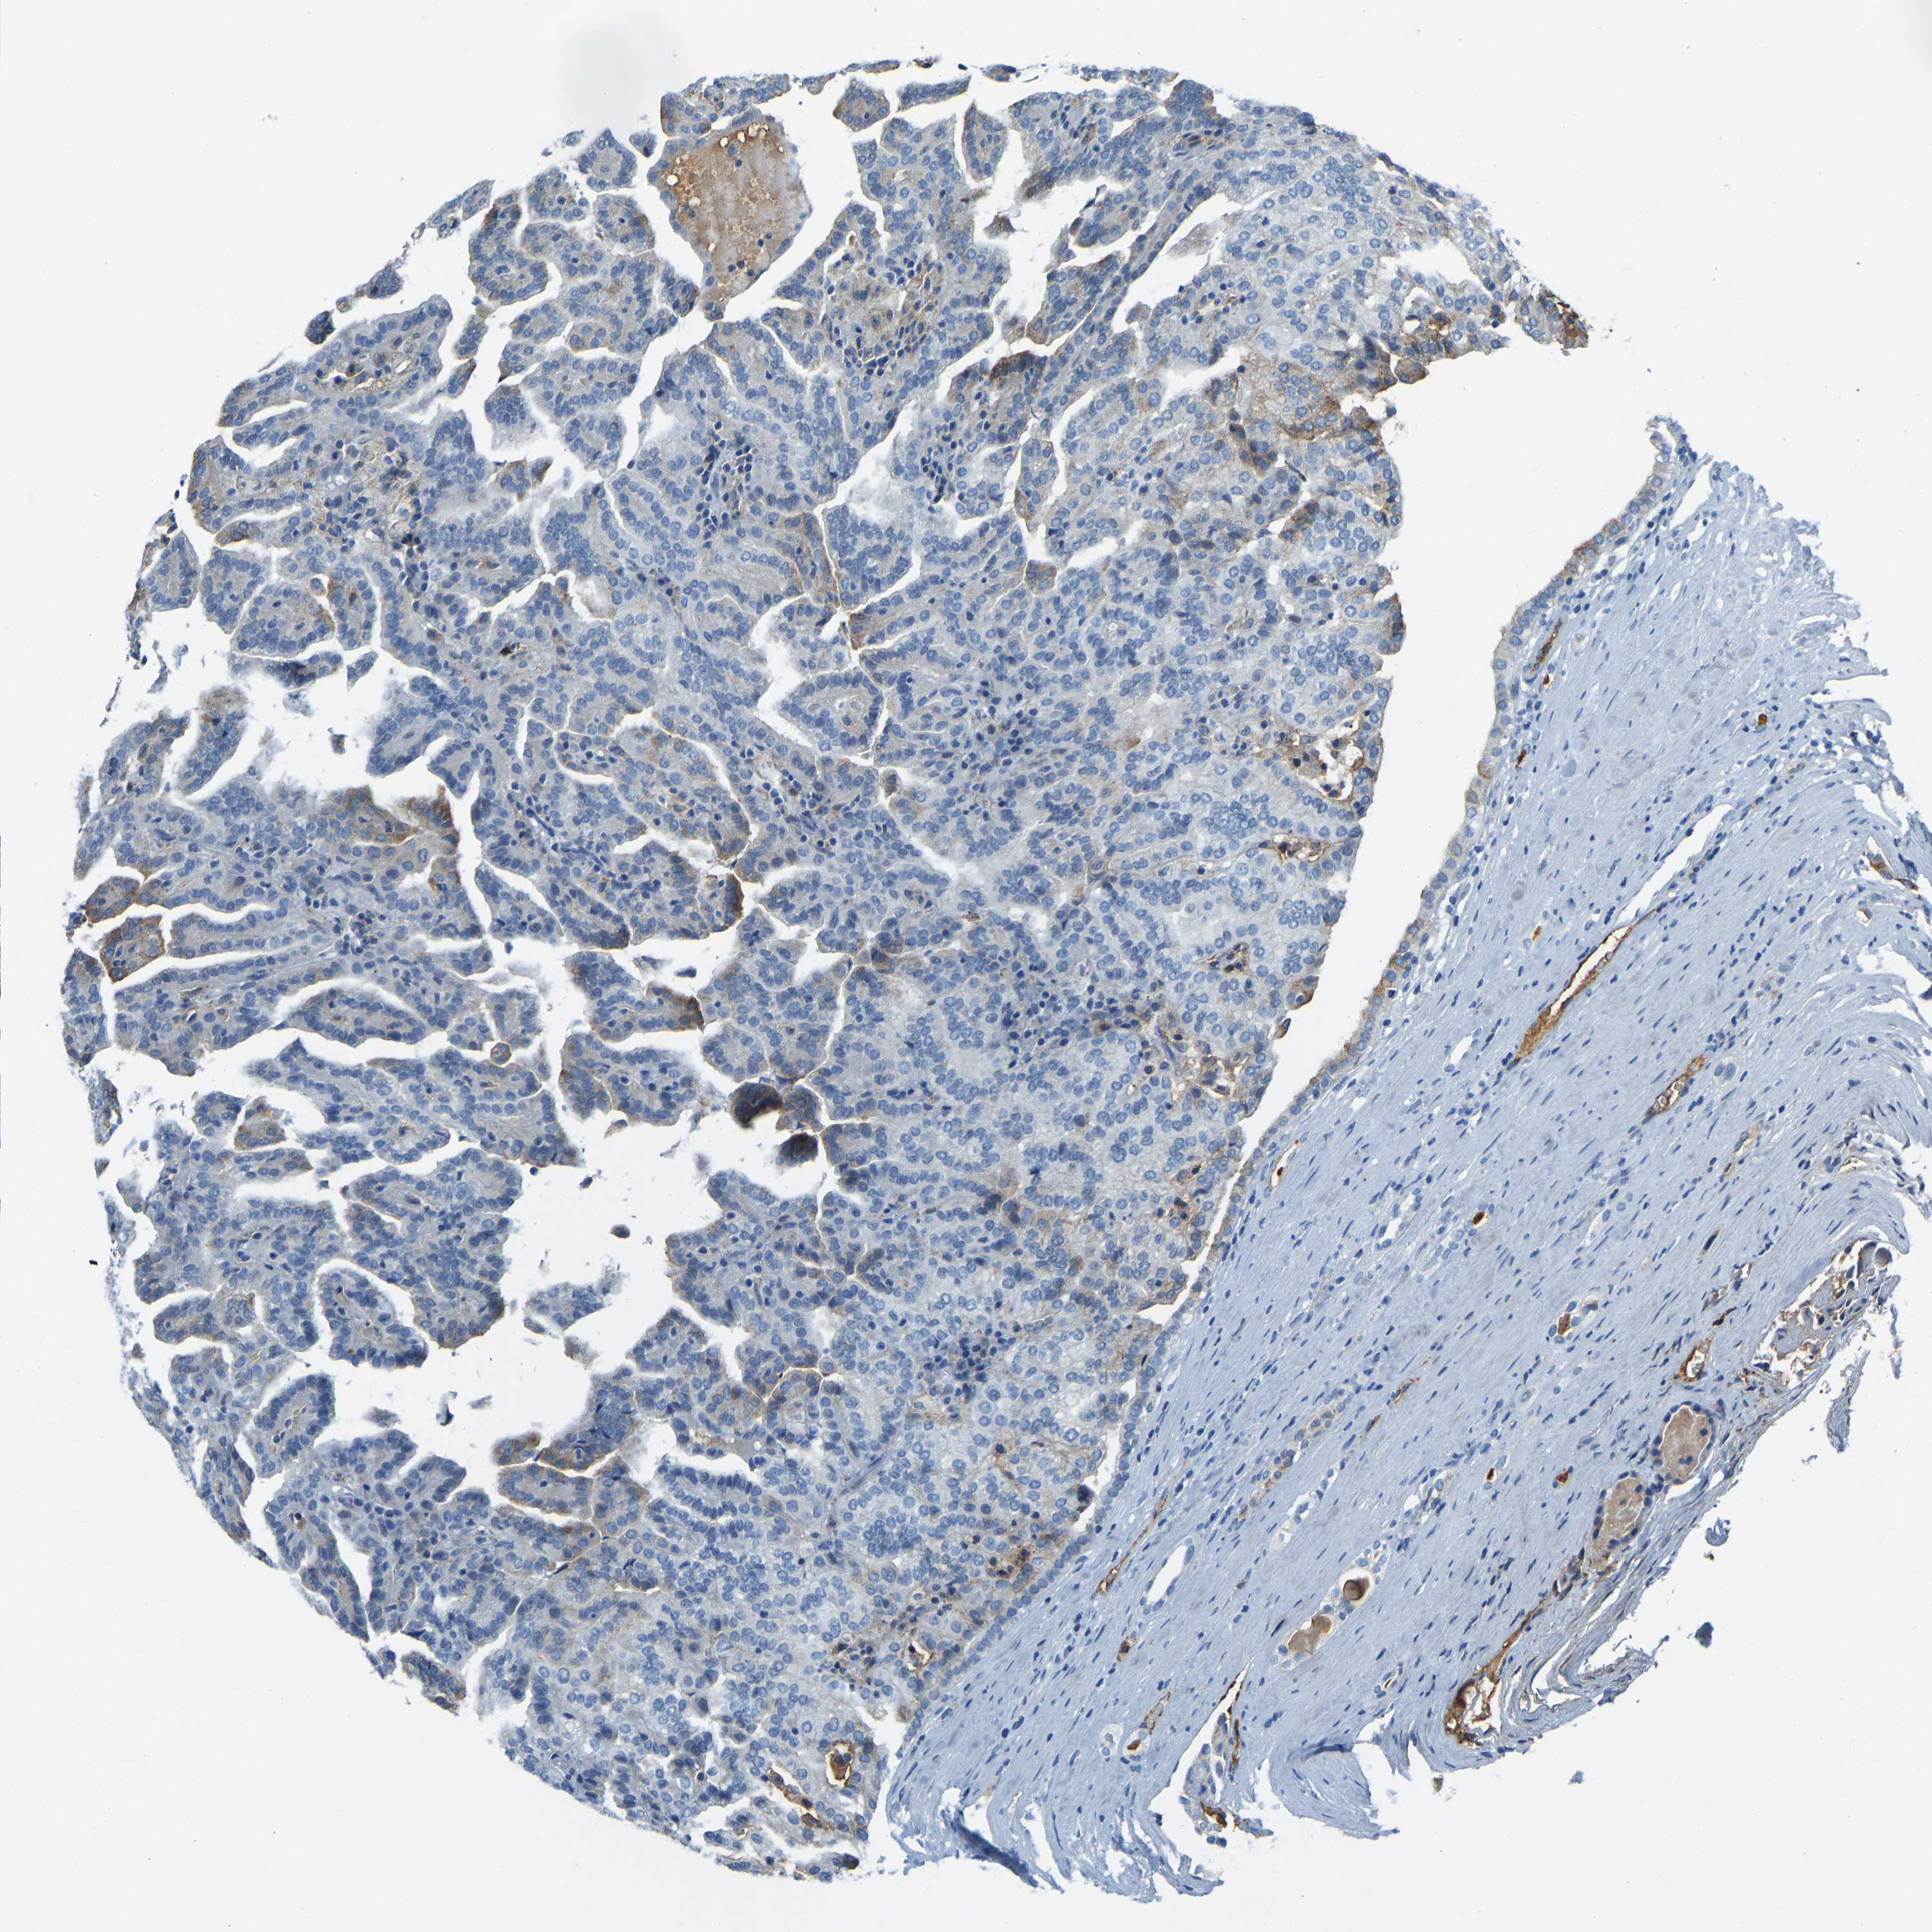

KIDNEY RENAL PAPILLARY CELL CARCINOMA (TCGA) - Interactive survival scatter ploti

The Survival Scatter plot shows the clinical status (i.e. dead or alive) for all individuals in the patient cohort, based on the same data that underlies the corresponding Kaplan-Meier plots. Patients that are alive at last time for follow-up are shown in blue and patients who have died during the study are shown in red.

The x-axis shows the expression levels (FPKM) of the investigated gene in the tumor tissue at the time of diagnosis. The y-axis shows the follow-up time after diagnosis (years). Both axes are complimented with kernel density curves demonstrating the data density over the axes. The top density plot shows the expression levels (FPKM) distribution among dead (red) and alive patients (blue). The right density plot shows the data density of the survived years of dead patients with high and low expression levels respectively, stratified using the cutoff indicated by the vertical dashed line through the Survival Scatter plot. This cutoff is automatically defined based on the FPKM cutoff that minimizes the p-score. The cutoff can be changed by dragging the vertical line or by entering a cutoff value in the square labeled "Current cut-off".

Under the Survival Scatter plot the p-score landscape (black curve; left axis) is shown together with dead median separation (red curve; right axis). Dead median separation is the difference in median mRNA expression between patients who have died with high and low expression, respectively. It is calculated as follows: median FPKM expression of dead patients with high expression - median FPKM expression of dead patients with low expression. This is intended to aid the user in visually exploring custom cutoffs and the associated p-scores and dead median separation.

Individual patient data is displayed and can be filtered by clicking on one or more of the category buttons on the top of the page. Categories describing expression level and patient information include: high, low, alive, dead, female, male and tumor stages. The scale of the x-axis can be toggled between linear and log-scale by clicking on the "x log" button. Mouse-over function shows TCGA ID, patient information and mRNA expression (FPKM) for each patient.

& Survival analysisi

Kaplan-Meier plots summarize results from analysis of correlation between mRNA expression level and patient survival. Patients were divided based on level of expression into one of the two groups "low" (under cut off) or "high" (over cut off). X-axis shows time for survival (years) and y-axis shows the probability of survival, where 1.0 corresponds to 100 percent.

THBS4 is not prognostic in Kidney Renal Papillary Cell Carcinoma (TCGA)

Best expression cut offi

Based on the FPKM value of each gene, patients were classified into two groups and association between prognosis (survival) and gene expression (FPKM) was examined. The best expression cut-off refers the FPKM value that yields maximal difference with regard to survival between the two groups at the lowest log-rank P-value. Best expression cut-off was selected based on survival analysis .

When clicking on this number, the vertical dashed line indicating cut-off, the interactive survival plot, and the Kaplan-Meier curve will be adjusted to show results based on the best expression cut-off.

: N/A